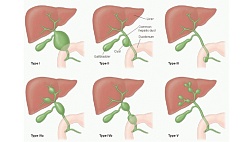

Внутри желчного пузыря на его стенке бывают выросты. Их называют полипами.

Бывают доброкачественные полипы и злокачественные.

Они могут мешать, могут вести себя как камни в желчном пузыре, но рак из них обычно не вырастает. Сюда относят холестероз, аденомиоматоз, воспалительные полипы и аденомы.

Аденомиоматоз желчного пузыря - это разрастание слизистой оболочки в стенке желчного пузыря. Звучит страшновато, но на самом деле это не настоящая опухоль. Рак из него обычно не вырастает.